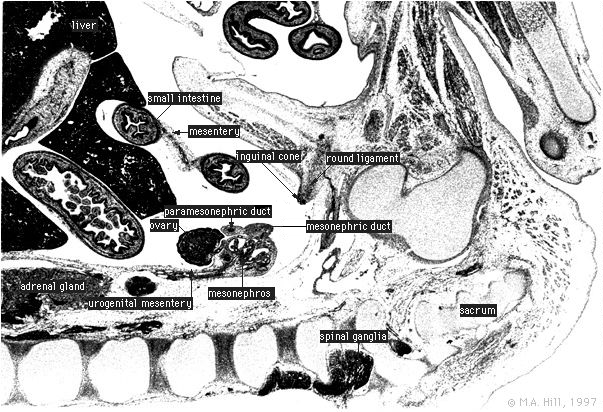

Human Embryo

Labelled Sagittal Section

High power only Labelled

Labels for paramesonephric and mesonephric ducts have been transposed on disc.